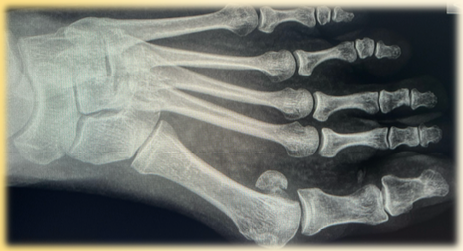

Hallux valgus